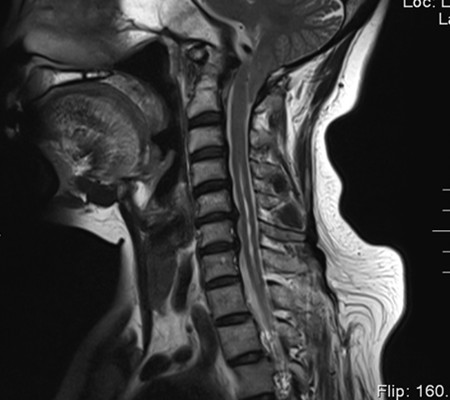

患者,女,53歲,以“頸肩部麻木、疼痛10月”入住神經(jīng)外科一病區(qū)。該患者小腦扁桃體下疝畸形,頸椎先天發(fā)育也有異常。

主任劉增強(qiáng)、責(zé)任總醫(yī)師巨濤等人就此病例進(jìn)行了多次討論。術(shù)前第一次運(yùn)用先進(jìn)的3D打印技術(shù)重塑了患者的寰枕部骨質(zhì)及血管,證實(shí)了患者先天性寰椎后弓缺如。經(jīng)過充分的術(shù)前準(zhǔn)備,顯微鏡下切除了下疝的小腦扁桃體,結(jié)合3D打印結(jié)果,歷時4小時完成了我院第一例后路減壓+枕頸內(nèi)固定術(shù)?;颊咝g(shù)后3天下床活動,10天出院。